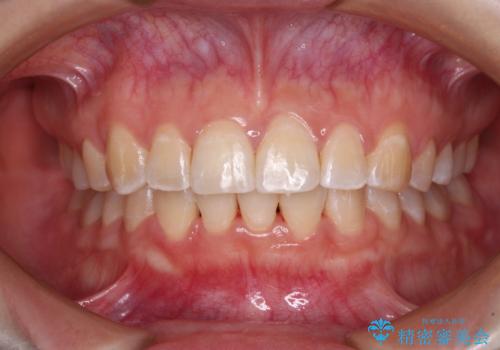

気になる出っ歯をインビザラインで改善

- 上の前歯が出っ歯であることを気にして来院された患者様です。

上の歯列全体が前方に突出している咬み合わせであったので、事前に補助装置を用いて、上の歯列全体を後方に移動させ、その後上下歯列をインビザラインで整えることとしました。

治療期間は長くなりましたが、出っ歯が改善することができました。

治療を行いながら、果たして奥歯の咬み合わせを改善することができるのかという不安はありましたが、結果としては理想的な咬合を獲得することができました。

口が閉じやすくなり、患者様には大変満足していただきました。